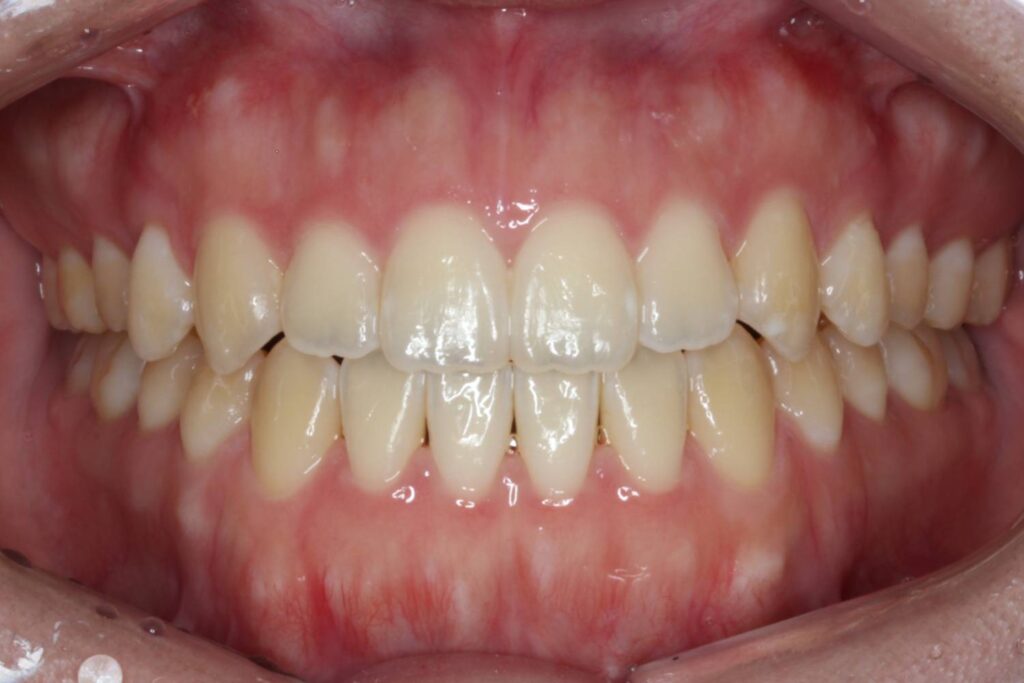

After

インビザラインは臼歯を「圧下」させることによって前歯を伸び出させずに開咬を治せるため、開咬に適した装置と言えます。

治療後は前歯もしっかりと噛み合うことで、機能的な歯並びを獲得することができました。